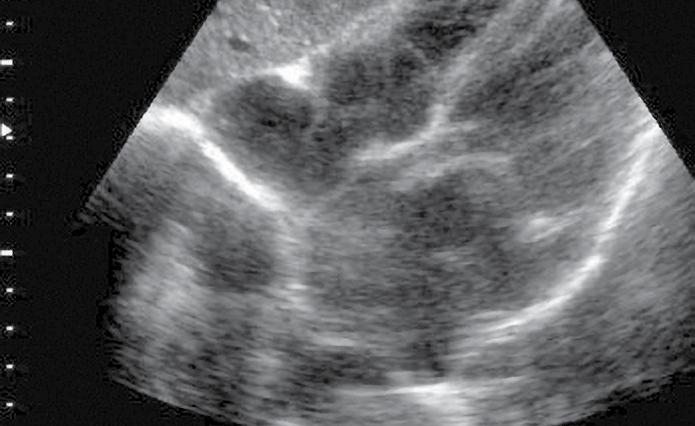

• contractilitatea globală a ventriculului stâng, identificând mărimea și statusul contractil – prezența unei insuficiențe cardiace acute (fig.2) cu necesitatea administrării medicației diuretice, inotrope, vasoactive în funcție de parametrii hemodinamici și corelarea cu aspectul plămânului și a venei cave; vizualizarea unui ventricul stâng hiperkinetic, cu reducerea volumui cavității (fig.3) ceea ce indică corelat cu aspectul VCI cu diametru redus (fig.4) o stare de hipovolemie ce necesită administrarea de fluide;

• aprecierea mărimii ventriculului stâng comparativ cu cel drept – identificarea unei supraîncărcări a ventriculului drept, cu suspiciunea de cord pulmonar acut (fig.5) și necesitatea de administrare de trombolitic pentru trombembolism pulmonar;

Fig.3. Secțiune subxifoidiană. Cord hiperkinetic (cavități reduse)

Fig.5. Secțiune subxifoidiană. Cord drept dilatat

Fig.7. Secțiune intercostal drept. Colecție Spațiul Morrison

Fig.8. Secțiune longitudinală suprapubiană Colecție recto-vezicală